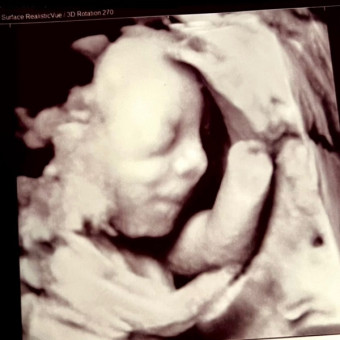

Maya's Baby Registry

Maya Metcalf

Welcome to my baby registry!! These items are essentials and some cute things to gift baby Charlotte Elizabeth. I have some postpartum items listed in case anyone wanted to help me out with those as well! Thank you so much for thinking of me and baby girl. You are so appreciated🫶🏼